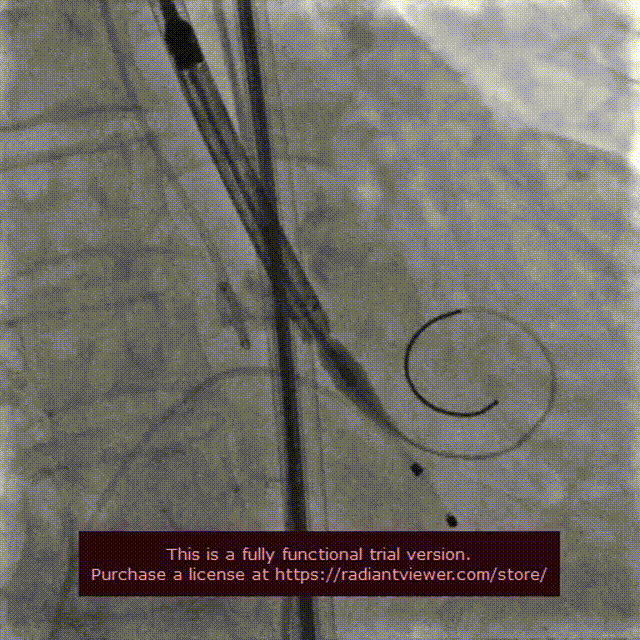

主动脉根部造影

18 mm球囊预扩

输送系统定位

VenusA-Plus®释放过程